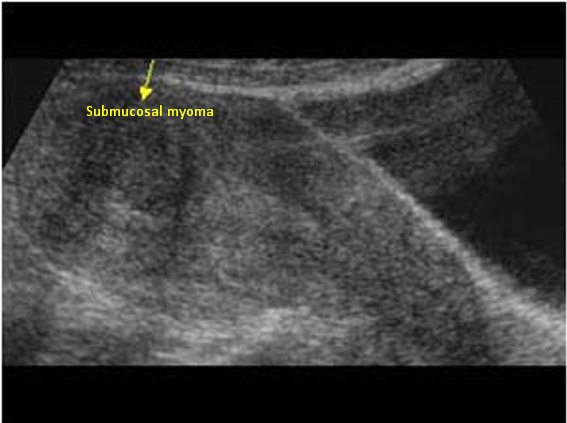

Myoma patients presented to the gynecology clinic due to complaints of prolonged menstrual bleeding and dysmenorrhea. During the transvaginal ultrasound (TVUS) examination, an intramural myoma was detected in 105 patients, submucous myoma in 35 patients, and intramural and submucous myoma detected in 60 patients (Figs. 1,2). Ovarian endometriosis was present in 105 of these patients. These patients were operated on by gynecologists. Pathology results were compatible with leiomyoma uteri (Fig. 3). The hospital stay was for 2 days. In the postoperative period, surgical site infection developed in 6 patients and hematoma at the incision line in 3 patients. Hematoma drainage was performed in only 1 patient. Surgical site infection resolved with antibiotic treatment. During the follow-up period, abdominal wall endometrioma developed only in the patient who underwent intervention due to myomectomy + ectopic pregnancy at the same time (0.5%). Characteristics of the 3 groups are shown in Tables 3,4.

Fig. 2. Transvaginal ultrasonography of submucous myoma.